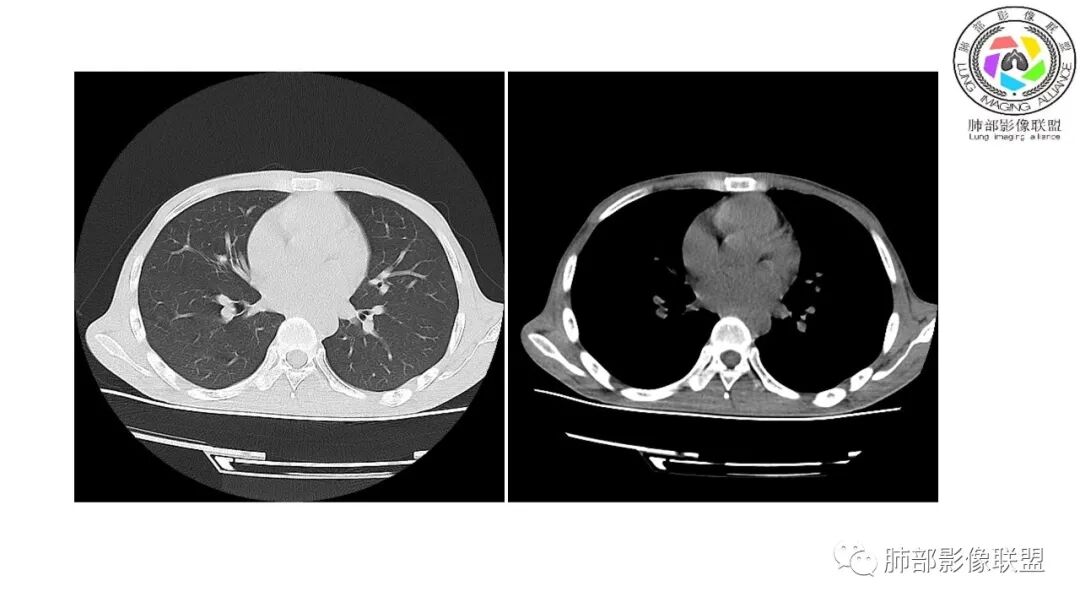

南边:12日好一些

南边:支持炎性,结合病史,马尼首选

影像与临床:1.青年男性,HlV阳性,颜面部皮疹(未提供皮疹图像)、发热(高热),实验室CRP、PCT高,T-Spot阴性。2.右肺下叶空洞结节,壁厚不均,边界清楚,其内线状影,未见液平及钙化,未见卫星灶,纵隔淋巴结增大,双侧腋窝见增大淋巴结。心腔内低密度提示贫血可能。肝脾影增大,未见结节影及块影。腹膜后见多发增大淋巴结。

综合分析:本例肺部影像学改变并不具有特征性,空洞性病灶须与多种疾病鉴别,但年轻HIV阳性患者,高热,皮疹,肝脾增大,纵隔、腋窝、腹膜后见多发增大淋巴结等都强烈提示马尔尼菲篮状菌感染的可能性。